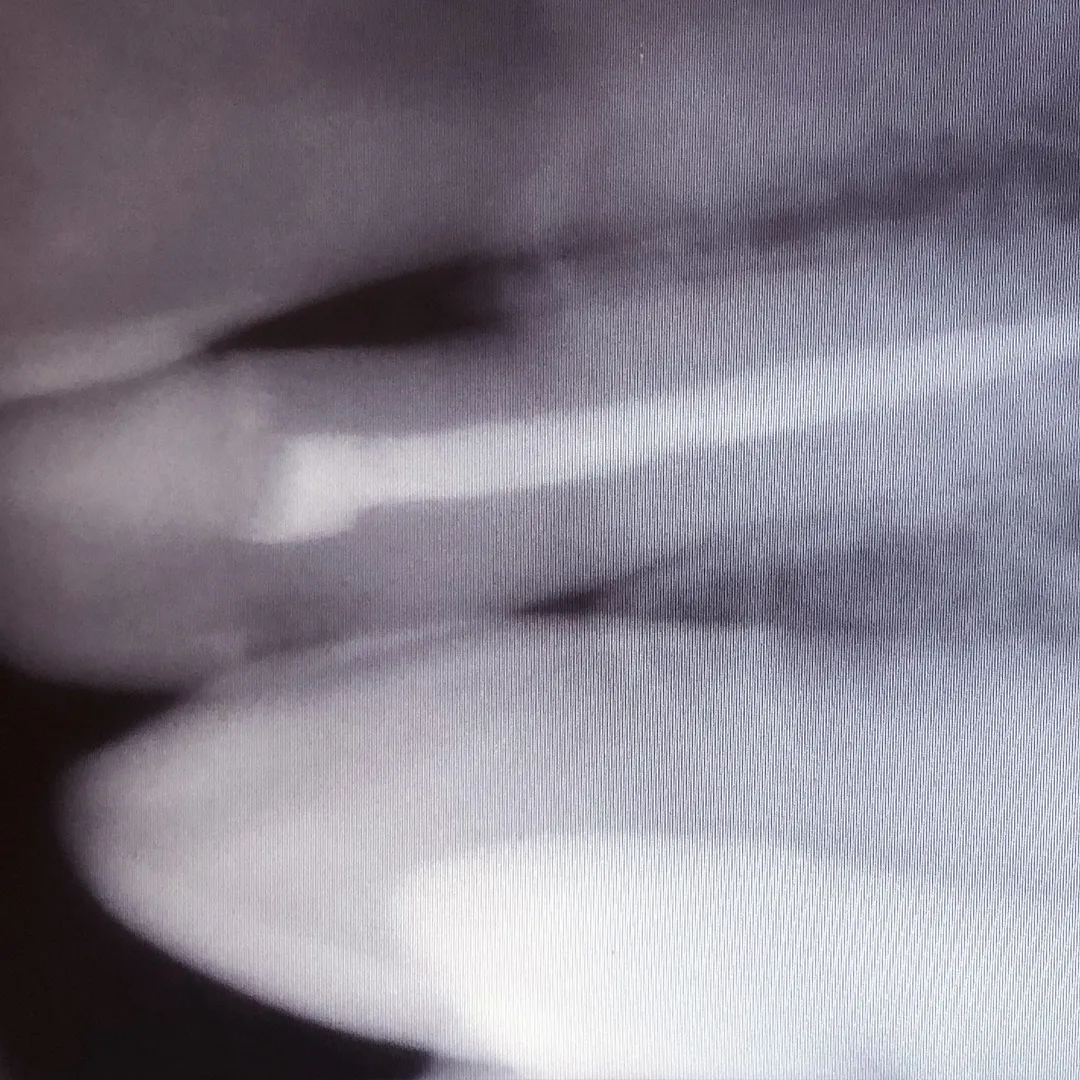

- постоянная пломбировка 3 каналов ;

- рентген-контроль.